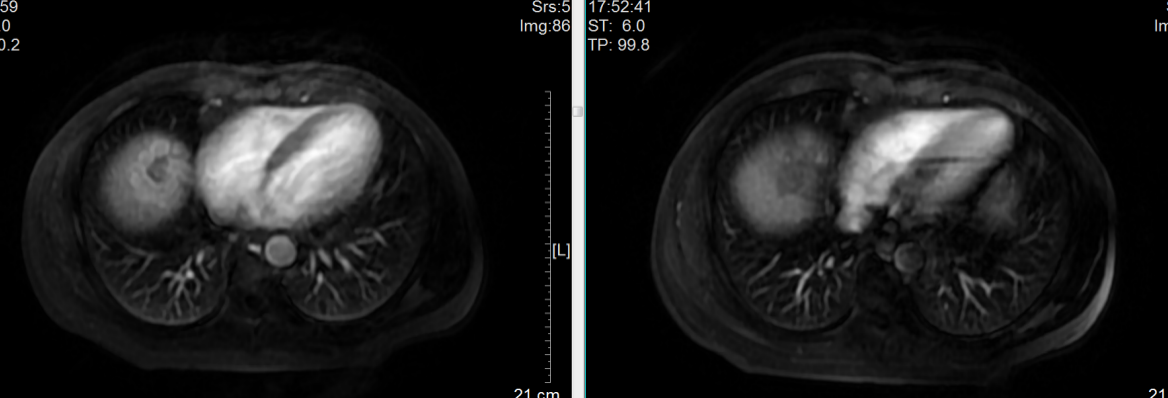

术后即时PET-CT显示钇90放射性微球完全分布在肿瘤内,正常肝实质未受影响

MRI显示疗效达到完全缓解(CR)